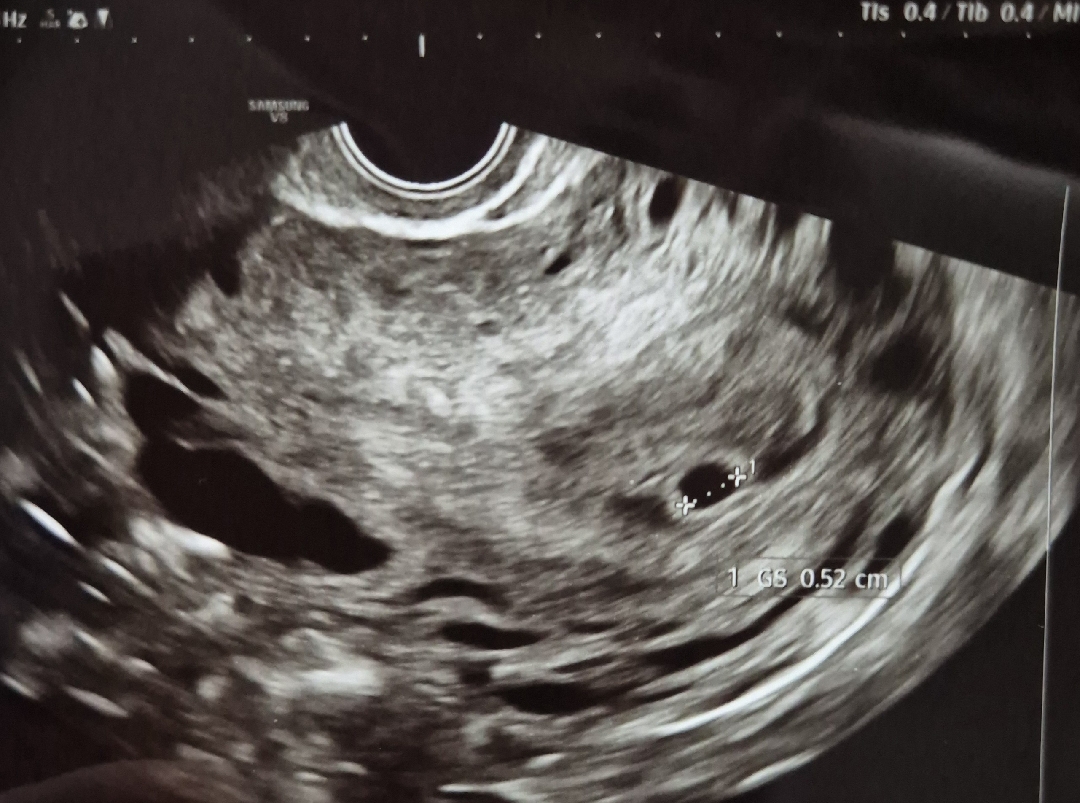

15일차 피검 316.6 18일차 1500 19일차 집들이 완료!!! 💖 0.52cm로 작디작고 소듕,,🥹🥹